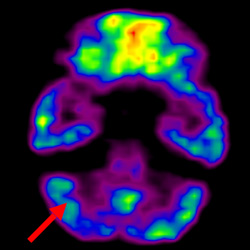

細胞治療前 PET CT 掃描顯示神經組織中的藍/黑色區域,表明腦癱引起的大腦損傷。

細胞治療后,藍色和黑色區域減少,并且看到更活躍的區域。這表明損傷減少并改善了大腦功能。

這證明細胞療法是治療腦癱兒童安全有效的方法。細胞療法可以更新大腦損傷的核心,并且可以通過 PET CT 掃描來監測大腦的改善情況。這些細胞療法與標準治療一起促進腦癱兒童的生長和改善。